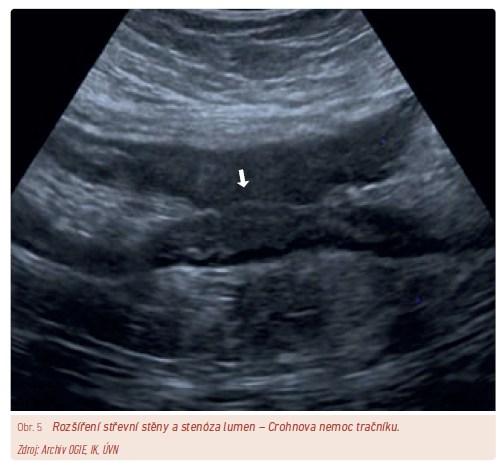

Ultrasonografie

Dominující postavení v zobrazovacích vyšetřeních má ultrasonografie pro svou bezpečnost, dostupnost, cenu a také absenci nežádoucích účinků. Ultrasonografie střeva je ale metodou značně expert‑dependentní, čímž je její dostupnost limitována. Častější je využití ultrasonografie u Crohnovy nemoci z důvodu transmurálního zánětu (obr. 5). Ultrasonografie u ulcerózní kolitidy je z důvodu slizničního zánětu lokalizovaného téměř vždy v rektu méně výhodná.

Největším přínosem ultrasonografie je její uplatnění v diagnostice i v monitorování terapeutického efektu a také v detekci komplikací (nitrobřišní abscesy, píštěle). Velmi vhodné je využití k odhalení časné pooperační recidivy, zvláště asymptomatické. Do klinické praxe jsou zaváděny metody ultrasonografie za použití kontrastní látky aplikované buď intravenózně (contrast enhacement ultrasound, CEUS), nebo perorálně (small intestine contrast ultrasound, SICUS), což zvyšuje senzitivitu při záchytu aktivity střevního zánětu nebo komplikací, nejčastěji stenóz.17